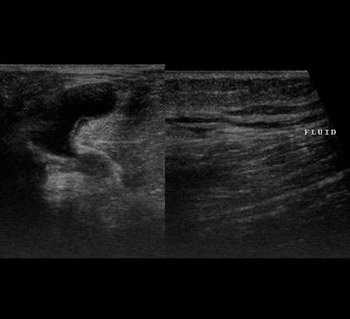

Anechoic cystic area seen behind the knee joint with adjacent fluid in soft tissues, suggesting ruptured Baker's cyst.